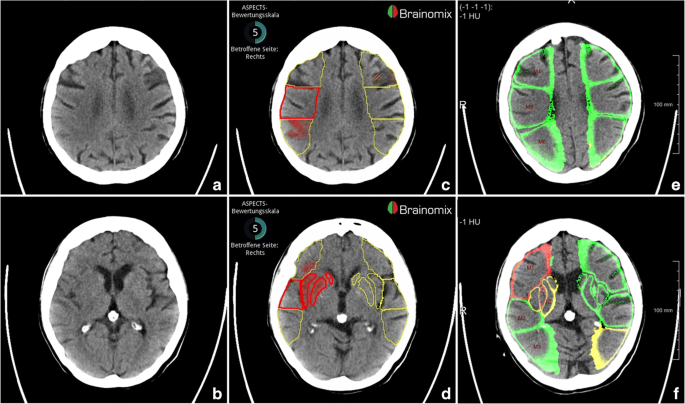

Aspects Score Ct : These subscores were summed to compute figure 2.

Aspects Score Ct / Alberta stroke programme early ct score.